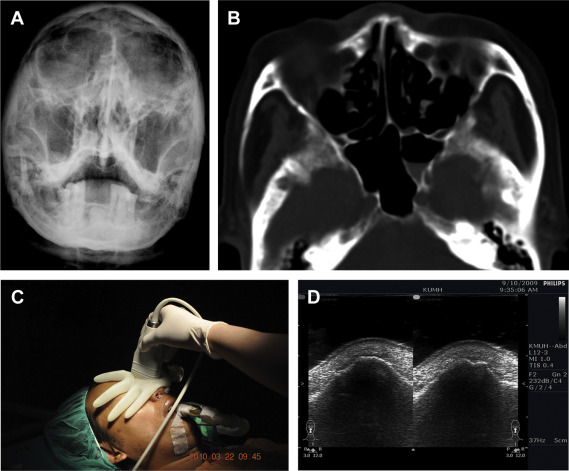

CANS was introduced in our emergency department in 2007. Since then, physicians have routinely used sonography to evaluate patients with acute nasal trauma except in cases of open wounds to the nose. During the study period, all CANS surveys were performed with a Philips Envisor HD ultrasound machine (Philips Medical Systems, Bothell, WA, USA) with a linear transducer (12 to 3 MHz; Fig. 1A–D). Transverse and longitudinal scans are both executed for the examiners panoramic evaluation. A water-filled surgical glove was used as a probe conductor to ensure full contact with the surface of the nose13 (Fig. 1C). In the study, any disruption, deviation, discontinuation of nasal cortical bone, or subcutaneous ectopic air noted over the scan site would be defined as nasal fractures. The examiner usually dichotomizes the survey result (fractured or nonfractured nose) with additional description of the injury site.

(A) Conventional Waters view showing negative findings and poor imaging quality ...

Figure 1.

(A) Conventional Waters view showing negative findings and poor imaging quality for nasal bone. (B) Axial CT showing a depressed fracture in the left lateral aspect of the nose without dorsum fracture. However, the right lateral aspect of the nose fracture is not visible. (C) The results of conductor-assisted nasal sonography performed after closed reduction can be immediately assessed in the operating room. (D) Axial sonography showing depressed fracture indicated by identical discontinuity over both the left and right lateral aspects of the nose. The right side fracture (arrow) was unrecognized by CT scan. CT = computed tomography.

However, application of ultrasonic gel on the nose may irritate the patients. Therefore, a water-filled glove is used to conduct ultrasound waves and obtains comprehensive images with comparable resolution. The CANS provides a full view of the bilateral nasal wall and enables identification of fine fracture lines (Fig. 1D). The definition for an accurate diagnosis is that sonographic survey allows the examiner to illustrate every detail of the fracture, such as disclosure of all the existing fracture lines, precise estimation of the extent of fracture (its severity, displacement amount, orientation, etc).